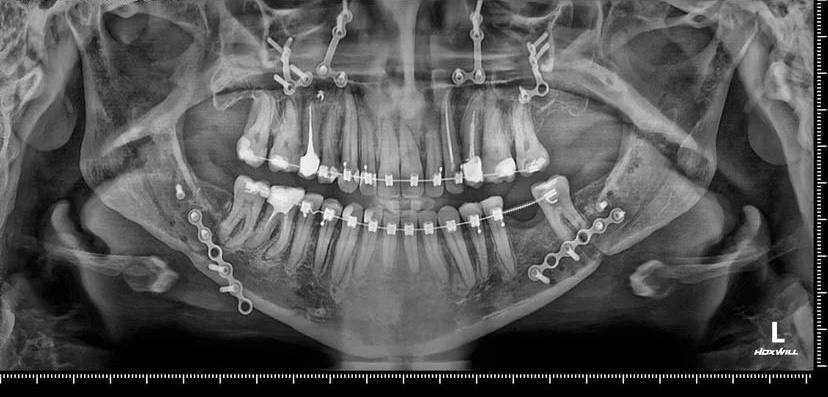

Волгоградские челюстно-лицевые хирурги Роман Стасюк и Анастасия Мулина прооперировали пациентку с зубочелюстной аномалией. Вмешательство, длившееся более шести часов, прошло в городской клинической больнице №1 региональной столицы.

После первого этапа лечения у врача ортодонта удалось достичь координация размеров зубных рядов. Затем в рамках комплексного подхода хирурги провели двучелюстную остеотомию. Такую операцию назначают, когда консервативные методы уже не действуют.

Через четыре месяца пациентка сняла брекет-система. Ей стало легче кушать, улучшился внешний вид.